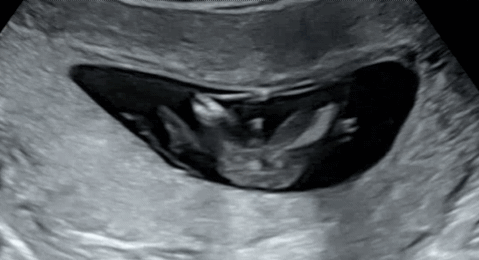

12주 1차를 무사히 넘겼습니다. 니프티도 한 상태인데 2주뒤에 결과가 나와서요. 정밀 초음파 선생님께서는 아빠닮은거 같네요. 하시길래 이시기에 딸도 튀어나와 있지 않나요? 하니 그럼에도 불구하고 그렇게 말한거는 그냥 말한건 아니겠죠? 하시면서 하지만 아직 담당의는 말씀 안해주실거에요. 일단 우리끼리만 그렇게 알고 있고 정확한건 좀 더 기다려 봐요. 하셨는데 첫째가 딸이라 아들을 원하고 있기는한데 아들맘분들 보셨을때 어떠셨나요? 제 지인중에는 아들이라고 했다가 딸이라고 바뀐경우도 있긴한데 저정도면 아들 맞는거겠죠..? 처음봐서 잘 모르겠어요.